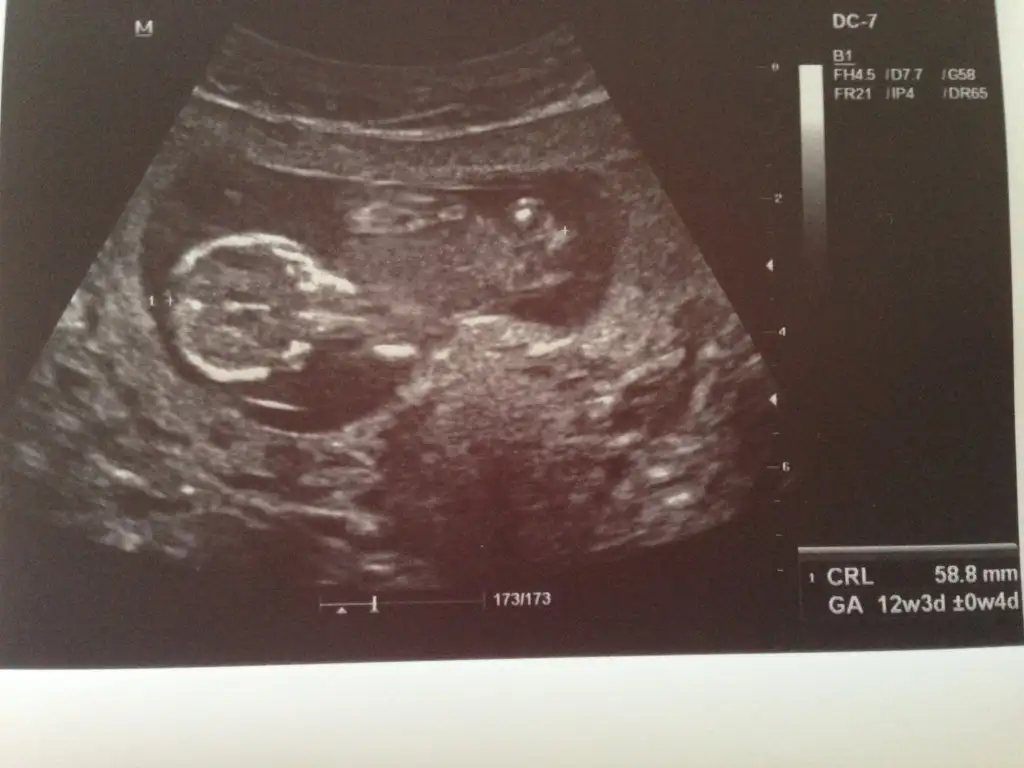

Erkek bence yalniz nub icin erkek annesi 12 . Haftayi bekleKızlar sizce nedirEki Görüntüle 1535231

Dr birşey söylemedimi pekiKizlar 12+4 haftalikmis bebegim bakarmisiniz acaba tahminleriniz nedir ben anlayamadim

yorum yaparmısınız arkadaşlar .iki yeni resim daha yükledim lütfen yorumlarınızı bekliyorum

20 haftalığım bende hala öğrenemeynlerdenim .yorum yaparmısınız arkadaşlar .